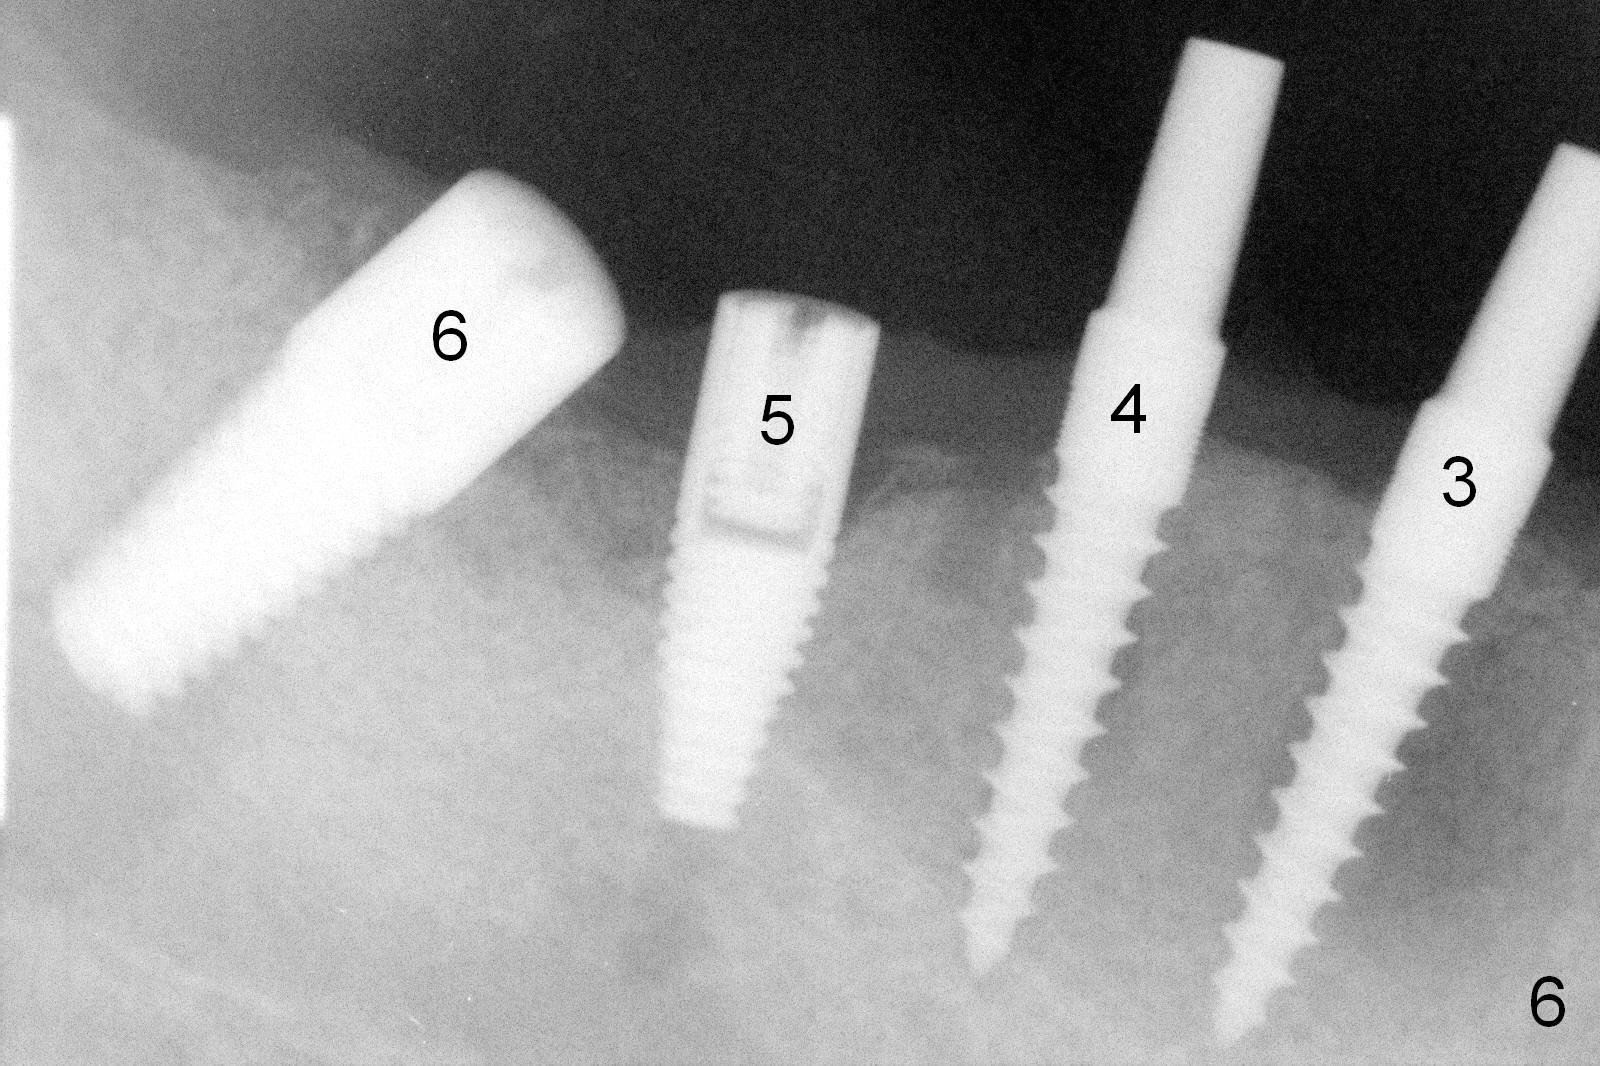

The lower right bridge (from canine (Fig.2: 3) to 1st molar (Fig.1: 6)) fails while a 77-year-old man is undergoing chemotherapy for urinary bladder cancer.  The abutments of the bridge are extracted without plan for implants (Fig.4).   Four months later, the patient returns for implants (Fig.3), but the ridge is narrow (Fig.5).  While 2 of 3x14 mm 1-piece implant are placed at the canine and 1st bicuspid sites, 2 piece ones at the 2nd bicuspid and 1st molar sites (Fig.6: 3.5x11 mm, 5x14 mm).  Soft (Fig.7-10) and hard (Fig.11) tissues heal 1 week (Fig.7) and 4 months (Fig.8-11).  There is minimal bone resorption 1 year 7 months post cementation (Fig.12,13, non-splinting).  It appears that narrow diameter implants are a valid solution to narrow ridge at the sites of the lower canine and premolar.  As long as there are enough implants for function, the crowns are not necessary to be splinted.  Surprisingly, the patient starts flossing after implant restoration.  Retrospectively an immediate provisional bridge should have been fabricated.